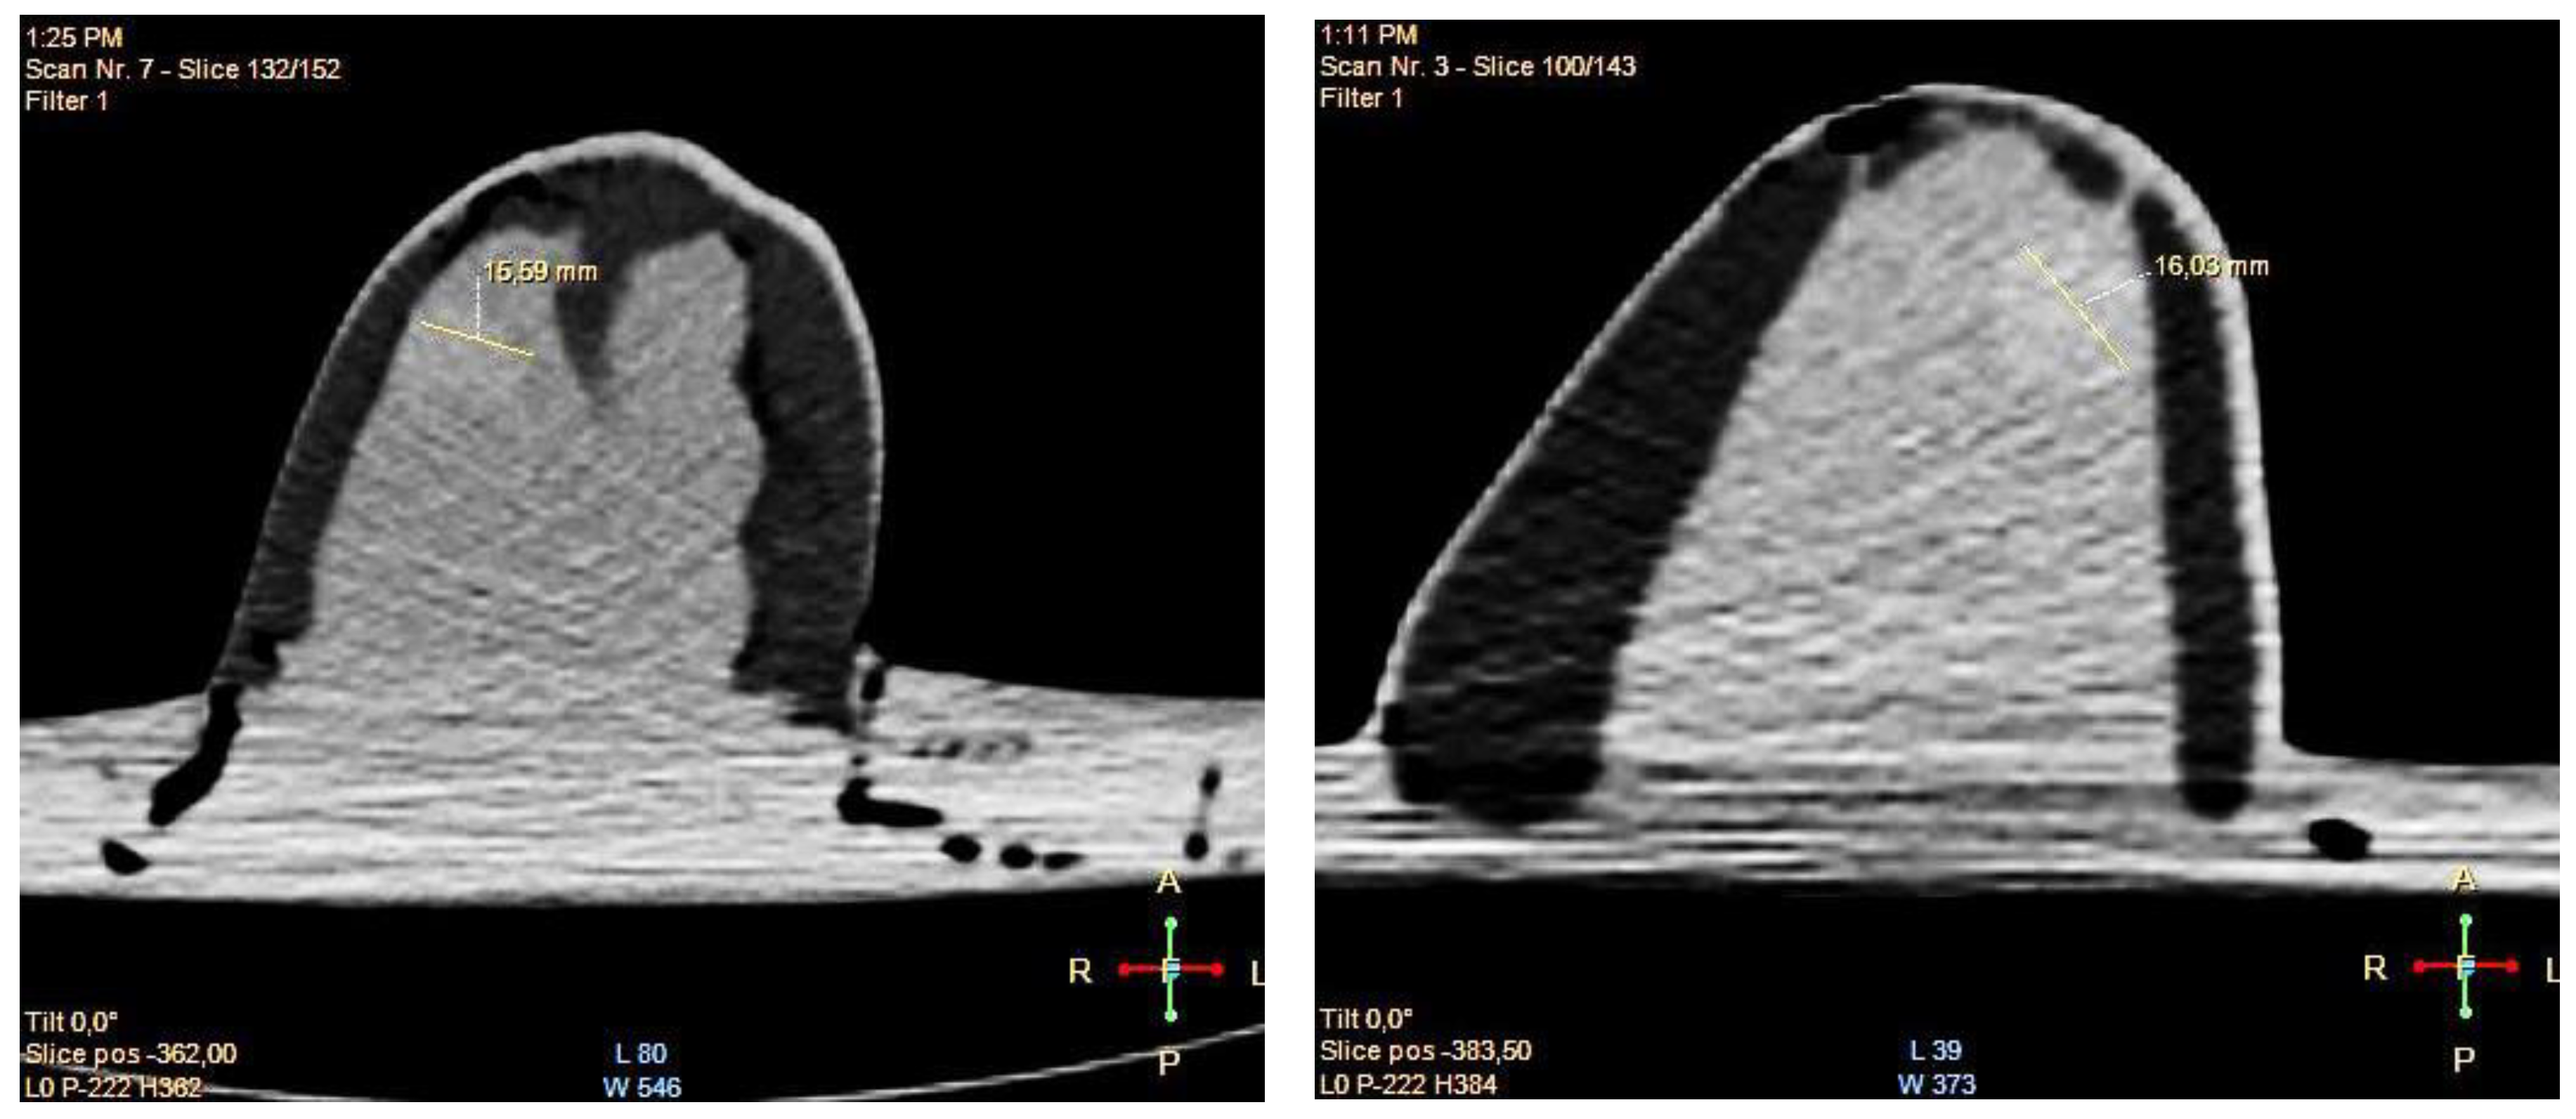

- Digital mammography scanning of Phantom A was performed with a Mammomat Novation DR system (Siemens Medical Solutions, Germany). The phantom was vertically taped to the device to reproduce the position of the breast during a mammographic exam (Figure 7). However, no compression was applied to the phantom as the fat-mimicking material was not elastically compressible. As a result, a poor contrast was observed between tumor and fibroglandular tissue. Phantom A was imaged at Mo/Rh 28 kVp and 140 mAs (Figure 8a) and at Mo/Rh 34 kVp and 160 mAs (Figure 8b), with a pixel spacing of 0.07 × 0.07 mm2, focal spot 0.3 mm and FOV 286 × 233 mm. The relative lack of contrast between the tumor and fibroglandular tissue was as a result of the lack of breast compression used during the acquisition, due to the lack of compressibility of the phantom materials. However, the relative contrast displayed between the fibroglandular and the tumor TMMs with the slightly higher kVp was slightly better. The bright external surface in each image is the skin TMM, while the darker irregular structure next to the skin is the subcutaneous fat TMM. The saturated white region is the fibroglandular tissue and the tumor mimic is within the red square; the contrast definition between both of these tissue types was challenging, which was representative of the clinical situation where dense breasts are imaged. Finally, as mentioned above, there was slightly better contrast between the fibroglandular tissue mimic and the tumor mimic with the slightly higher kVp. The same low contrast appears in the CT scanning results, performed with a Symbia TruePoint SPECT-CT scanner (Siemens Medical Solutions, Germany). The CT images were acquired at 80 kVp and 36 mAs, with a pixel spacing of 0.97 × 0.97 mm2 and slice thickness of 2 mm. In both phantoms, the tumor was localized using the MRI datasets as reference (Figure 5). Representative CT images of the phantoms are presented in Figure 9. As for the mammography images, a similarly low contrast was observed between the tumor and fibroglandular tissue. Nevertheless, the CT images demonstrated superior resolution of the internal structures, for example, showing the subcutaneous fat TMM fingers penetrating inside the fibroglandular layer.